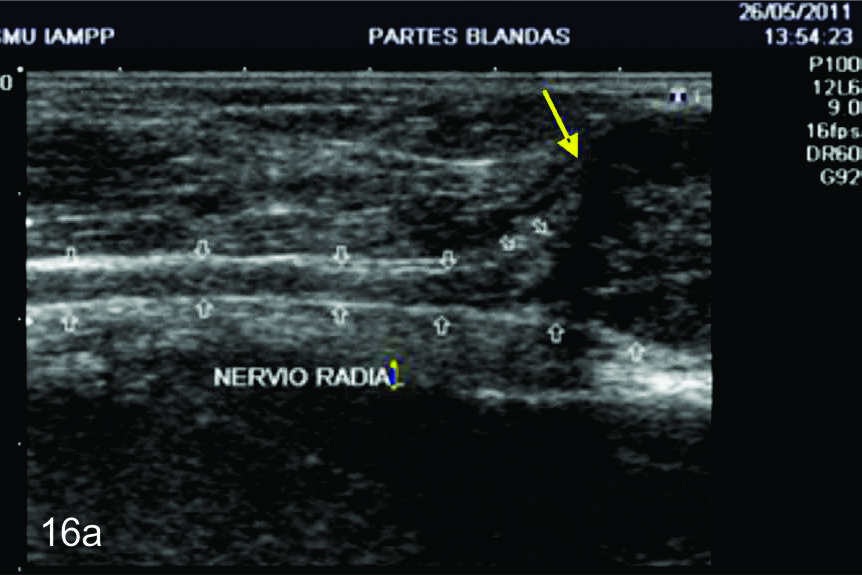

Figura 14 a y b

Lesión traumática del plexo braquial luego de accidente en moto.

A y B- cortes comparativos transversales al plexo braquial al nivel del espacio interescalénico (A-derecho patológico y B-izquierdo sano), se demuestra la asimetría de las estructuras del plexo. RS- tronco superior, RM-tronco medio, RI-tronco inferior, EP- músculo escaleno anterior, EAM-músculos escalenos medio y anterior.

Figura 14 c y d

C y D- cortes comparativos longitudinales sobre el tronco medio del plexo braquial (C- izquierdo sano y D- derecho patológico), se demuestra la asimetría de la raíz media del plexo, la cual se demuestra en un corte longitudinal comparativo (señalada entre calipers amarillos). La flecha blanca en D señala un fragmento óseo desplazado debido a una fractura del proceso transverso vertebral que generaba conflicto con la raíz.